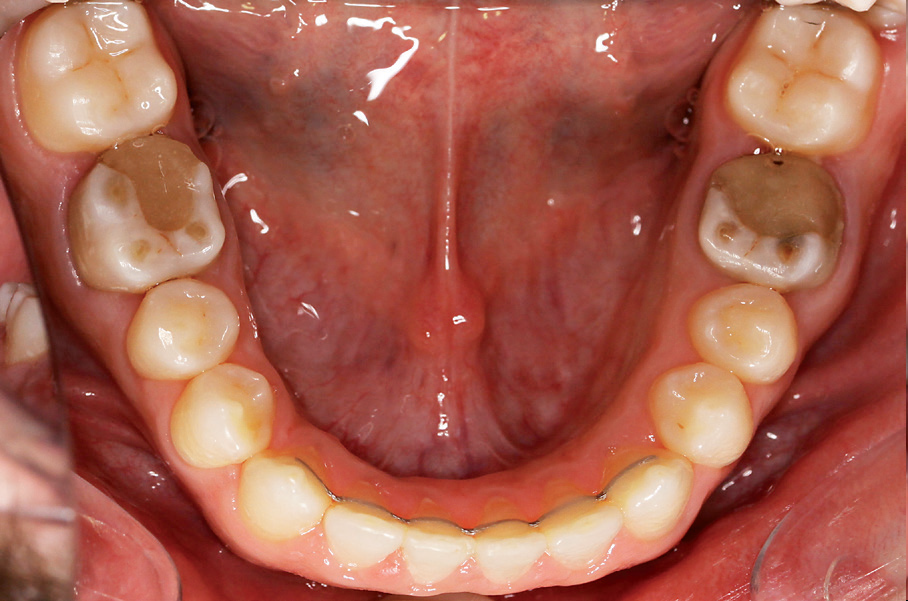

- Opis dwóch przypadków pacjentów ze zdiagnozowanym zgryzem otwartym w odcinku przednim spowodowanym przez spoczynkowe doprzednie położenie języka.

Streszczenie: Pomimo dostępności wielu metod leczniczych zgryz otwarty jest uważany za jedną z najtrudniejszych do leczenia wad ze względu na dużą liczbę nawrotów. Za ponowne otwarcie się zgryzu najczęściej odpowiedzialne jest nieskorygowane doprzednie położenie spoczynkowe języka. Celem pracy było przedstawienie leczenia zgryzu otwartego w odcinku przednim przez korektę nieprawidłowego położenia języka za pomocą ostrej zapory w łuku górnym. Materiał. Opis dwóch przypadków pacjentów ze zdiagnozowanym zgryzem otwartym w odcinku przednim spowodowanym przez spoczynkowe doprzednie położenie języka.

Zgryz otwarty w odcinku przednim jest rzadko spotykaną (1,5-11%) (1) wadą zgryzu charakteryzującą się występowaniem szpary niedogryzowej pomiędzy przednimi zębami (2). Etiologia jest złożona i obejmuje wpływy środowiskowe oraz indywidualny wzorzec wzrostu uwarunkowany genetycznie. Wśród czynników środowiskowych wyróżnia się między innymi: ssanie palca (najczęściej kciuka), przedłużone stosowanie smoczków, ustny [...]